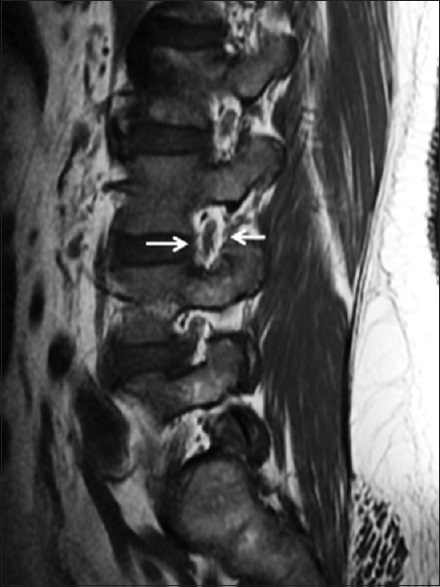

Cross-sectional Study on Incidental Spinal Findings in Magnetic Resonance Imaging Lumbar Spine of Patients with Low Back Pain

Dr. Binoj Varghese, Arun C Babu, Ashok Kumar, PS Priya, Jaison S John, Mohammed Noufal, KM Sivasubramaniyan (Author)

38-44

Magnetic Resonance Imaging of Lumbosacral Intervertebral Discs in Nigerians with Low Back Pain

Ademola Joseph Adekanmi, Temitope Olugbenga Bello , Dr. Omolola Mojisola Atalabi, Kamaldeen O Jimoh, Oluremi Ayotunde Ogunseyinde (Author)

61-67

Pattern of Lumbosacral Magnetic Resonance Imaging Findings in Diagnosed Cases of Disc Degenerative Disease among Nigerian Adults with Low Back Pain

Uzoamaka Rufina Ebubedike, Eric Okechukwu Umeh, Godwin I Ogbole, CA Ndubuisi, Wilfred C Mezue, Samuel C Ohaegbulam (Author)

25-29